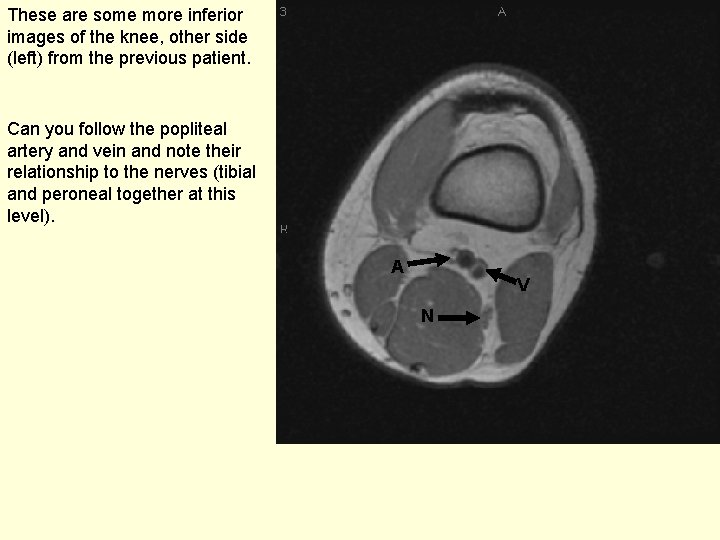

These are some more inferior images of the knee, other side (left) from the previous patient. Can you follow the popliteal artery and vein and note their relationship to the nerves (tibial and peroneal together at this level). A V N